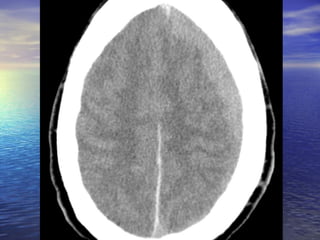

Diagnostic Imaging MRIis superior for demonstrating the size of an acute SDH and its effect on the brain, however noncontrast head CT is the primary means of making a diagnosis and suffice for immediate management purposes Noncontrast head CT scan (imaging study of choice for acute SDH) The SDH appears as a hyperdense (white) crescentic mass along the inner table of the skull, most commonly over the cerebral convexity in the parietal region. The second most common area is above the tentorium cerebelli Contrast-enhanced CT or MRI is widely recommended for imaging 48-72 hours after head injury because the lesion becomes isodense in the subacute phase In the chronic phase, the lesion becomes hypodense and is easy to appreciate on a noncontrast head CT scan

Summary Epidural HematomaPotential space between the dura in the inner table of the skull Can’t cross sutures Skull fractures in temporoparietal region Middle meningeal artery Lenticular or biconvex shape Lucid interval Common in alcoholics Medical emergency CT without contrast Evacuate via burr holes Subdural Hematoma Between the dura mater and the arachnoid mater Can cross sutures Cortical bridging veins Crescent shape Loss of consciousness Common in elderly Common in alcoholics Medical emergency CT without contrast Evacuate via burr holes